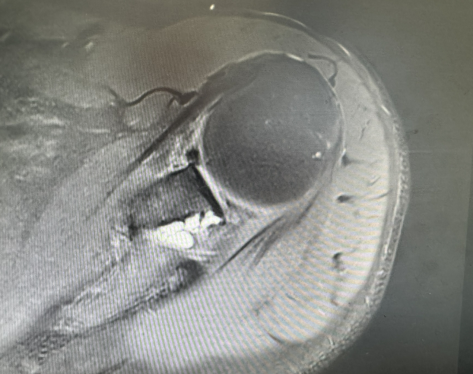

本次手术的李先生,近1年来一直被左肩部顽固性麻木困扰,严重影响了日常生活和工作。辗转多种保守治疗无效后,慕名来到大连市第二人民医院。阮文礼主任经详细问诊、体格检查及肩关节MRI、肌电图检查明确,李先生的冈盂切迹处存在一个直径约2*2*1厘米的囊肿,囊肿对周围的肩胛上神经造成了明显的压迫,导致神经传导功能受损,这正是引发其长期上肢麻木、影响生活的根本病因。

阮文礼团队采用超精准肩关节镜技术。手术中,阮文礼主任仅在患者肩关节开3个微小切口,将关节镜和手术器械置入关节内。借助高清摄像系统,观察到关节内冈盂切迹处的囊肿呈椭圆形,与周围组织粘连紧密。阮文礼清晰避开密集的神经血管网,小心翼翼分离囊肿与粘连组织,最终完整切除囊肿,并对受压的肩胛上神经进行彻底松解。整个手术历时1小时,全程“零误伤”,术后患者肩部麻木症状完全消失,肩关节活动功能恢复正常。